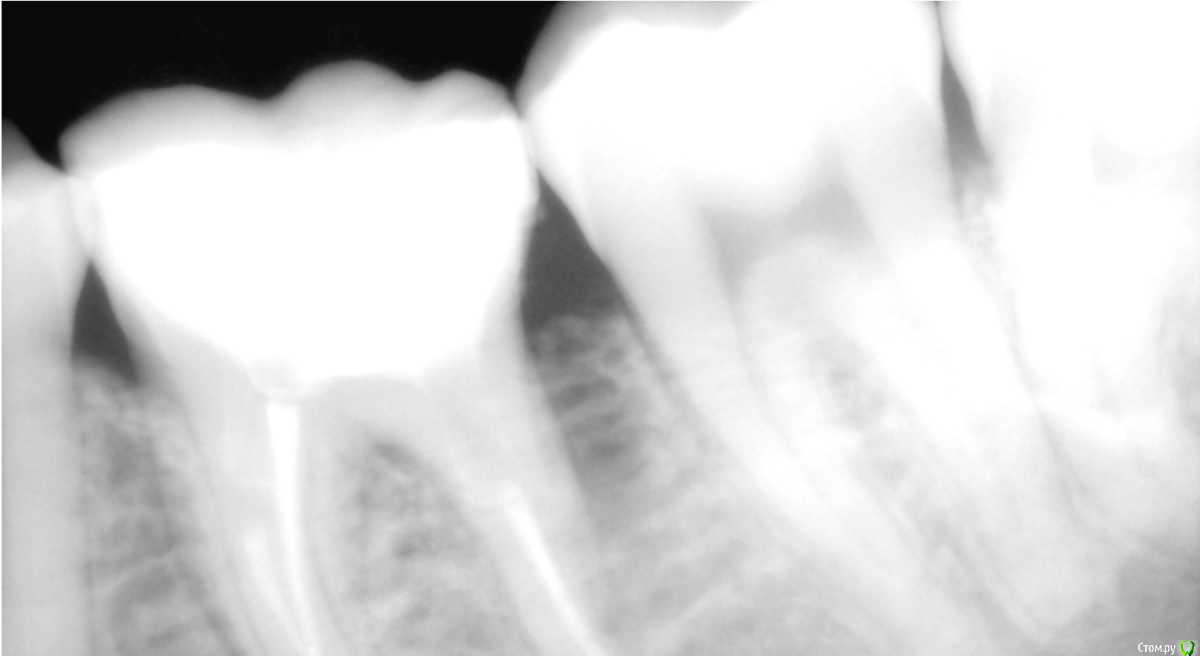

Melancholia Опубликовано 13 февраля, 2018 Поделиться Опубликовано 13 февраля, 2018 Депульпировали зуб месяц назад, нижняя 6 ка. Под временной пломбой откололась стенка зуба ниже уровня десны и началось воспаление десны, там где была эта стенка. Поставили постоянную пломбу которая очень большая(от моего зуба остался корень и одна стеночка), воспаление усилилось, температура 37,2, красная десна, кровоточивость,карман между десной и зубом, если надавить чуточка гноя, странные зудящие ощущения в десне, при ходьбе как будто пульс в этой десне. Пошла к другому врачу, сказали пломба нависающая, контактный пункт плохой и пломба недостаточно широкая из-за этого карман и все пр.Переделали большую часть пломбы. Было это две недели назад. Но воспаление не ушло. Карман ушел, сильная опухлость и покраснение десны ушли, но вечерами температура 37,2 , сбоку по краю зуба из десны торчит что-то красное, ощущения неприятные, но несильные, если нажать чуть-чуть, то десна в этом месте, где красное чуть чуть отходит и оттуда кровит немножко, откуда то будто изнутри, ощущения зуда вокруг зуба несильные. Гноя вроде нет, контактные пункты хорошие, нить проходит как надо. Полоскаю хлоргексидином, фурацилином, мажу Холисалом, временами ощущения легче, но до конца не проходит. Неделю назад показала своему стоматологу он сказал что стало лучше и что десна со временем пройдет. Никогда не было проблем с деснами, и нигде кроме этого места проблем нет. Сколько ждать? Почти месяц десна воспалена. Прилагаю рентген, до того как переделали нависающую пломбу, чтоб показать каналы, мало ли что.. нового снимка еще не делала, т.к. сказали что каналы норм и дело не в них. Зуб не болит, но поутру ощущение что он мешается, будто за ночь стал выше. Ссылка на комментарий